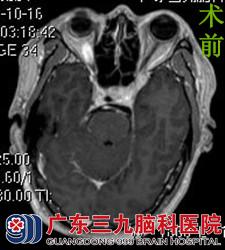

唐先生马上联系在广东三九脑科医院工作的侄儿,在侄儿的帮助下到医院行头颅MR检查,结果提示左侧眶尖区(肌锥外)示一不规则形异常信号影,增强后部分呈明显强化。综合神经外科的鲁明主任考虑脑膜瘤可能性大。在完善相关检查后,由鲁明主任主刀,在全麻及神经导航下行左侧视神经管探查+眶尖病变切除术,术中显微镜下见病变呈红褐色,伴有出血,边界不清,予分块切除,手术顺利结束。术后经过专科治疗护理,唐先生左眼视物较术前好转,未出现手术并发症,康复出院。术后病理结果:毛细血管瘤。